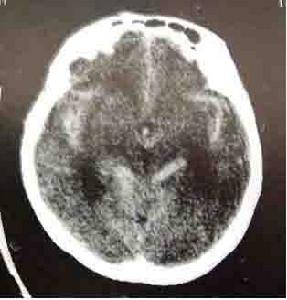

自發性蛛網膜下腔出血CT圖動脈瘤為最常見的出血原因大宗文獻統計表明動脈瘤出血占蛛網膜下腔出血病人的52%。此外,尚有一部分查不清死因者,其所占的比例受診斷條件影響,過去曾高達46.3%。隨著檢查手段的進步,對蛛網膜下腔出血的病因檢出率增加,不明原因的比例下降為9%~20%。血液病、顱內感染、藥物中毒等造成蛛網膜下腔出血者也偶見。

自發性蛛網膜下腔出血CT圖數蛛網膜下腔出血病例與吸菸有關,並呈量效依賴關係。經常吸菸者發生蛛網膜下腔出血的危險係數是不吸菸者的11.1倍男性吸菸者發病可能性更大。吸菸後的3h內是最易發生蛛網膜下腔出血的時段。酗酒也是蛛網膜下腔出血的好發因素,也呈量效依賴關係,再出血和血管痙攣的發生率明顯增高,並影響蛛網膜下腔出血的預後擬交感類物使用者易患蛛網膜下腔出血如毒品古柯鹼可使蛛網膜下腔出血的罹患高峰年齡提前至30歲左右。

自發性蛛網膜下腔出血CT圖1.連續放液,各試管內紅細胞計數逐漸減少。

自發性蛛網膜下腔出血CT圖血管痙攣也是蛛網膜下腔出血病人致死致殘的主要原因,約有13.5%的動脈瘤破裂引起的蛛網膜下腔出血病人因血管痙攣而死亡或殘廢。在致殘病人中約39%因血管痙攣而引起。